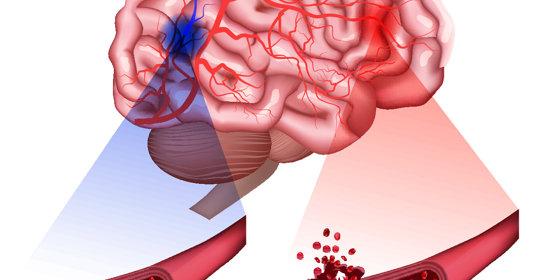

橋腦出血:中風復健方法與時間

橋腦出血:處理與預防措施

橋腦出血:治療措施與緊急性

橋腦出血:差異與治療